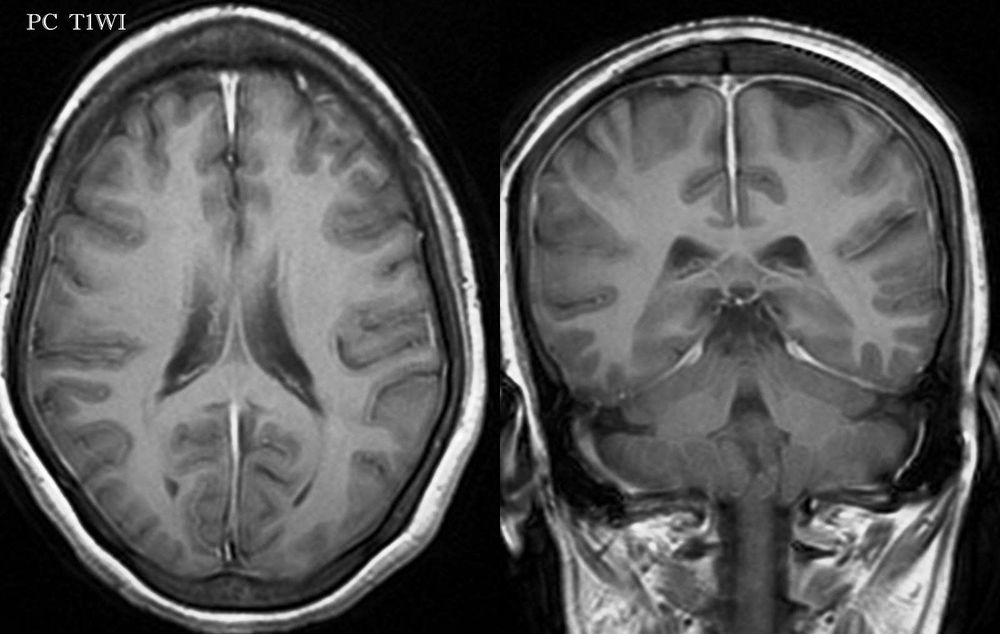

Để chẩn đoán bệnh viêm màng não thì bác sĩ sẽ phải thăm khám lâm sàng trên người bệnh, đồng thời sẽ kiểm tra họng, tai, cột sống…, khai thác những thông tin liên quan đến tiền sử bệnh lý hay nhiễm trùng gần đây của người bệnh. Ngoài ra, bác sĩ còn có thể kiểm tra xem trong máu của người bệnh có một số loại vi khuẩn nhất định hay không bằng phương pháp cấy máu định danh vi khuẩn hoặc chụp CT scan hay MRI cột sống để kiểm tra tình trạng sưng tấy. Để chẩn đoán xác định thì cần phải thực hiện thủ thuật chọc dò dịch não tủy được lấy từ cột sống để tìm xem nguyên nhân đến từ virus hay vi khuẩn.